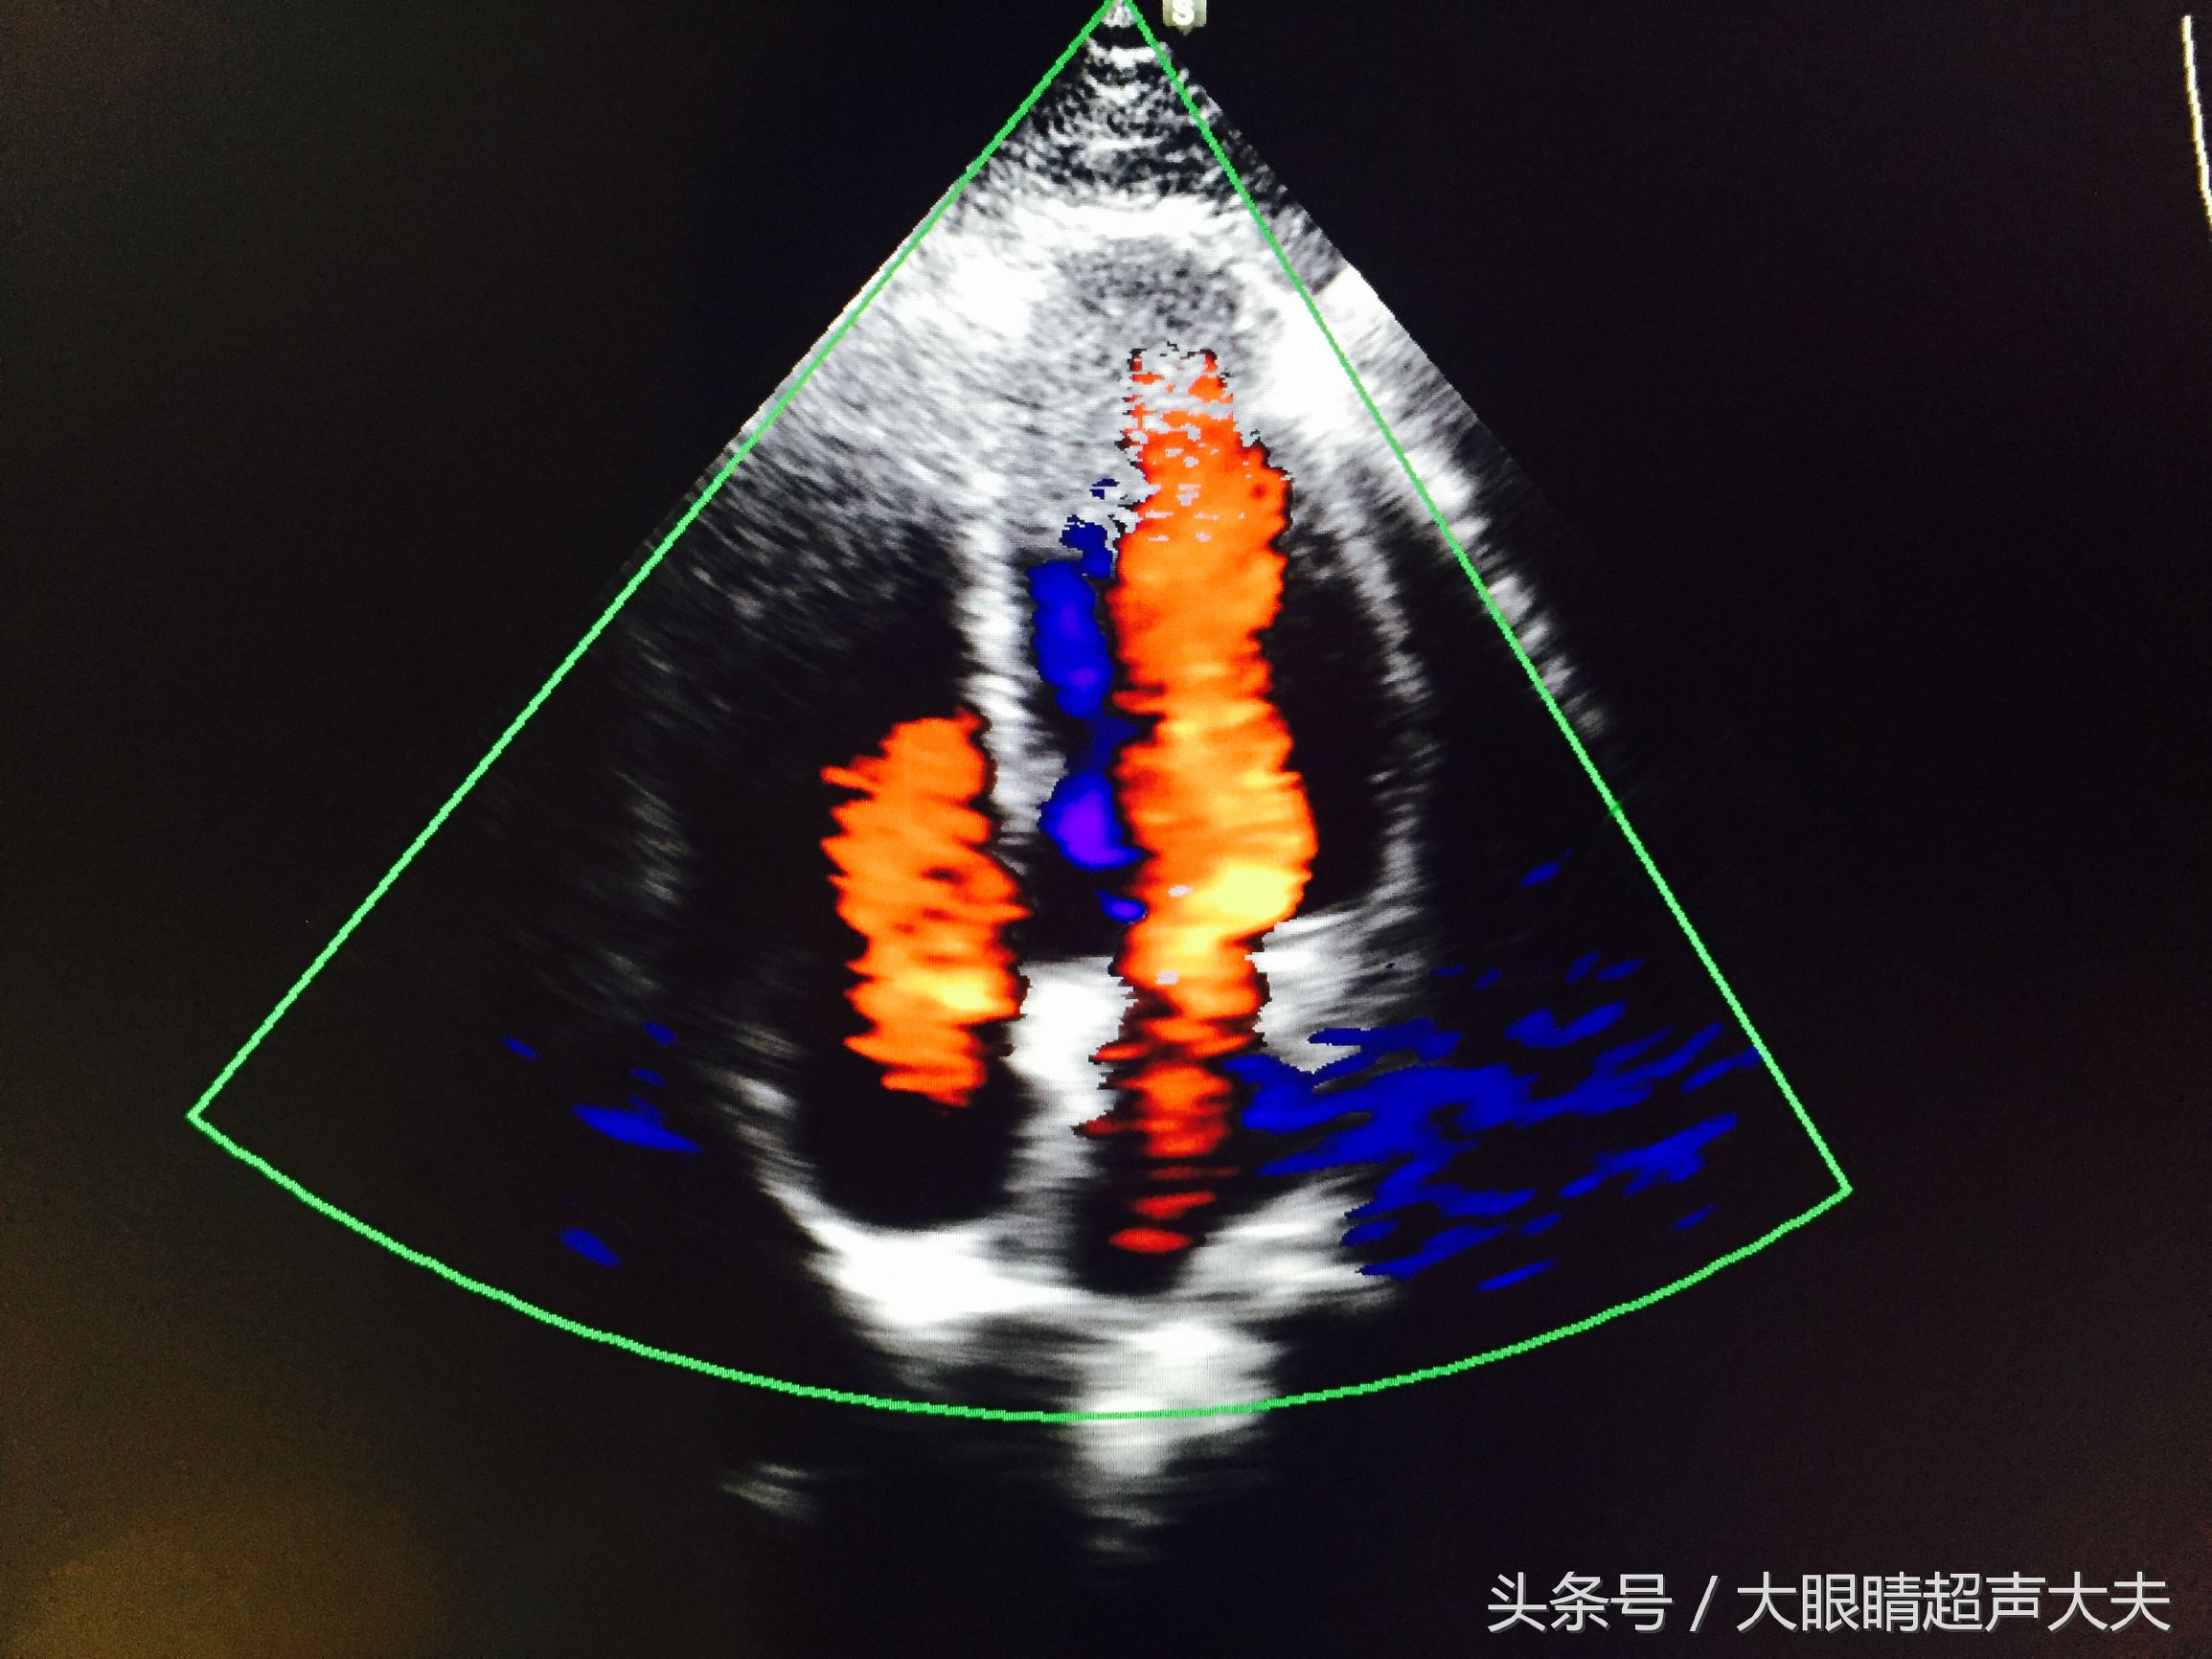

各种情境一样。而真正的彩超,是在黑白B超图像的基础上,当大夫需要知道某个脏器/部位的血供情况,某个结节/病变部位的血供情况(如上图中就是显示的一个甲状腺癌的血流情况),某根血管的走形情况的时候,大夫就会打出一个框框来,在框内会显示红蓝色的血流图像。而

这里的红蓝色并不是我们中学学生物时学到的红色代表动脉血,蓝色代表静脉血,不是的。这里的红蓝色代表着血流的

方向

。颜色的亮度代表着血流速度。医生再通过机器打出频谱,经过测量,可以得到某血管的血流速度,血流阻力,压差……等等各种指标。所以,彩超可以在黑白B超的基础上,又给医生提供了更多的信息,这样更加有利于疾病的诊断。

那么腹超就是医生把探头经过你的腹部去检查,看你身体内部的情况,就像图片1中我给大熊肚子上做B超一样,嘻嘻~。阴超/肛超就是将探头放进阴道/肛门里去检查盆腔脏器的情况。心超、眼超等就是专门检查心脏、眼睛等部位的超声检查(上图就是心脏彩超)。下图是眼超: